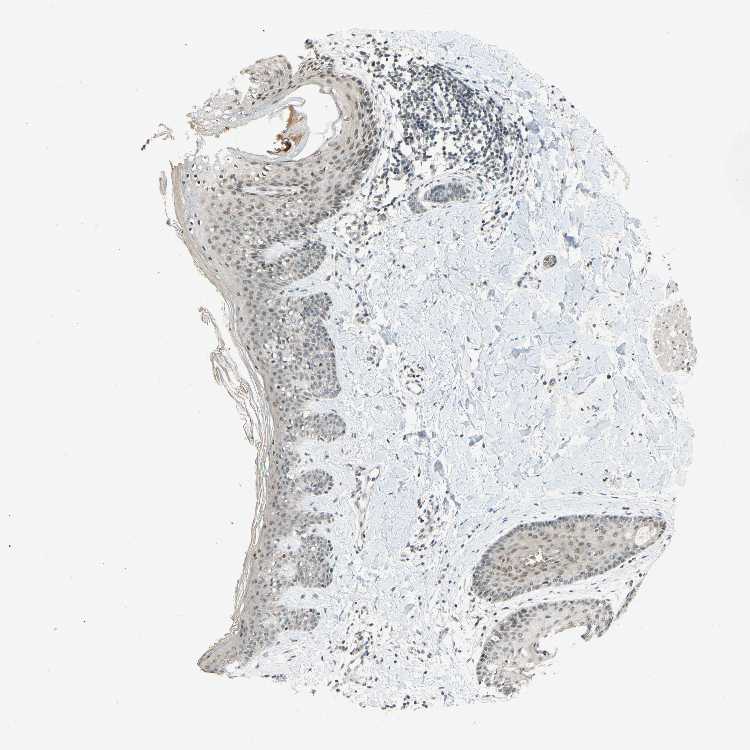

SKIN 1 - Antibody stainingi

Antibody staining in the annotated cell types in the current human tissue is reported as not detected, low, medium, or high, based on conventional immunohistochemistry profiling in selected tissues. This score is based on the combination of the staining intensity and fraction of stained cells.

Each image is clickable and will lead to virtual microscopy that enables deeper exploration of all samples and also displays staining intensity scores, fraction scores and subcellular localization as well as patient and tissue information for each sample.

Antibody HPA018248Antibody HPA019127Antibody CAB009196

Langerhans -LowLow

Cells in basal layer Low--

Cells in corneal layer Not detected--

Cells in granular layer Low--

Cells in spinous layer Not detected--

Eccrine glands Not detected--

Endothelial cells Not detected--

Extracellular matrix Not detected--

Fibroblasts -LowLow

Fibrohistiocytic cells Low--

Hair follicles Not detected--

Keratinocytes -MediumMedium

Langerhans cells Not detected--

Lymphocytes High--

Melanocytes MediumLowNot detected

Vascular mural cells Not detected--